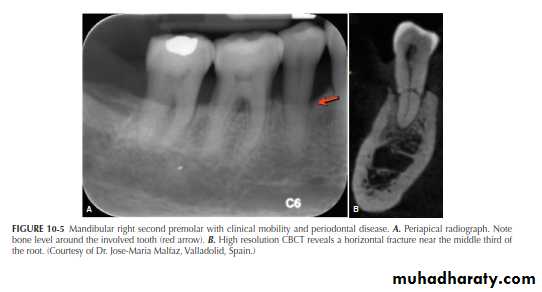

A major advantage of CBCT is the visualization of anatomic

structures in three planes, generally referred to as coronal, axial (transverse), and sagittal reconstructions. CBCT technology also allows for panoramic and oblique reconstructions in addition to anatomic-specific reformatting such as temporomandibular joint (TMJ) improved the sensitivity and specificity of accurately detecting lesions or conditions affecting the jaws

Currently, CBCT imaging is generally recommended for endodontic cases in which conventional dental radiographs may not yield adequate information